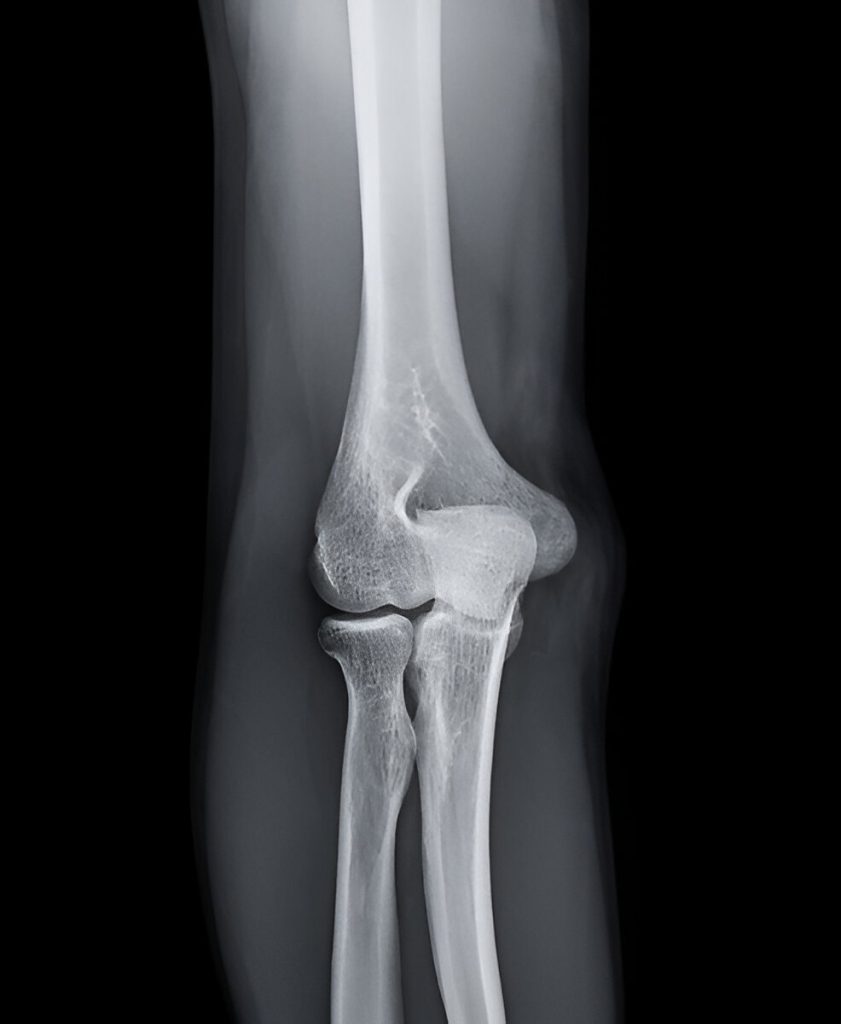

Olecranon Fracture

An olecranon fracture is a break in the bony tip of the elbow, part of the ulna—one of the two forearm bones. The olecranon forms the pointed end of the elbow and serves as the attachment site for the triceps tendon, allowing extension of the elbow.

This injury can vary from a simple, nondisplaced crack to a complex break with displacement, joint involvement, or multiple fragments. Because the olecranon is exposed and lacks protective soft tissue, it is particularly vulnerable to trauma.

• X-rays to assess the location, number of fragments, and displacement of the fracture